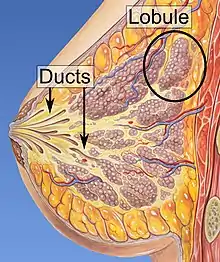

In anatomy, a lobe is a clear anatomical division or extension[1] of an organ (as seen for example in the brain, lung, liver, or kidney) that can be determined without the use of a microscope at the gross anatomy level. This is in contrast to the much smaller lobule, which is a clear division only visible under the microscope.[2]

Interlobar ducts connect lobes and interlobular ducts connect lobules.

Examples of lobules

Lobules of the mammary glands.

- the lobules of the mammary gland